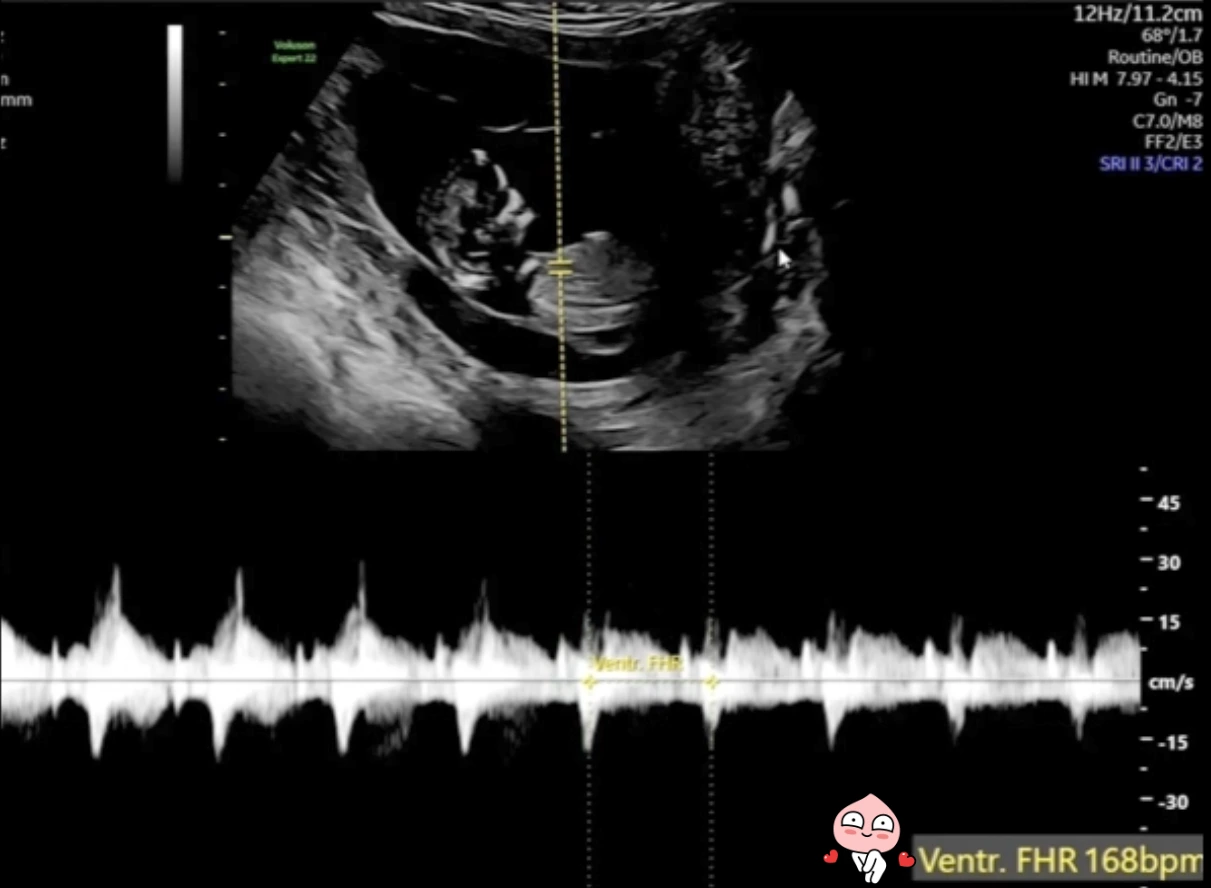

12주 태아 심박수 측정.PNG

[왼쪽은 태아 머리 크기와 임신 주수, 오른쪽은 심박수]

♬ FHR(Fetal Heart Rate)는 태아 심박수인데 168 bpm으로, 임신 12주 평균인 160~180 bpm의 범위 내 있으니 이 역시 지극히 정상적인 상태입니다.